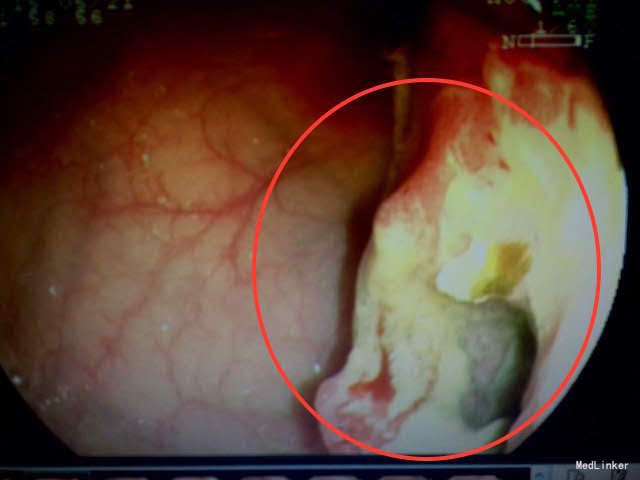

肠镜及活检结果:升结肠中-低分化腺癌。 治疗:腹腔镜右半结肠癌切除术,术后化疗。

随访:术后病理结果:升结肠中-低分化腺癌,如下图。 讨论:鉴别诊断:胃肠道肿瘤:多见中老年,可反复腹痛,可出现排便习惯或性状改变,晚期可出现肠梗阻症状,也可表现为全身症状,考虑可能性大,CT、肠镜及活检结果可明确诊断。胆石症:常表现为右上腹绞痛,可反射至背部,可出现黄疸,多与进食油腻食物有关,超声及CT可有助鉴别。